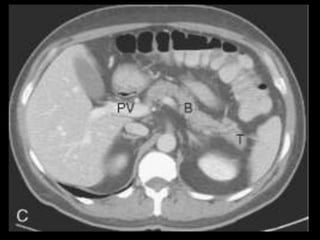

Pseudocistos

Coleções encapsuladas e uniloculadas de líquido

pancreático e material necrosado e proteináceo;

São necessárias 4 semanas ou mais para que um

pseudocisto evolua de uma coleção líquida aguda;

Mais comumente peripancreáticos, mas podem ser

observados no mediastino e na pelve;

Importância do contraste oral positivo;

Metade dos pseudocistos regride

espontaneamente;

Sintomas dependem

Pseudocistos-TC

Coleção líquida redonda ou oval, com uma parede

fina ou espessa, que apresenta intensificação pelo

contraste;

RM: lesão uniloculada bem definida, hipointensa

em T1 e hiperintensa em T2;

Bolhas de gás: infecção, fístula ou à cistostomia

interna;

Hemorragia aguda dentro do cisto: hiperdensa

Estenose ou oclusão venosa, com formação de

varizes ou pseudoaneurismas.